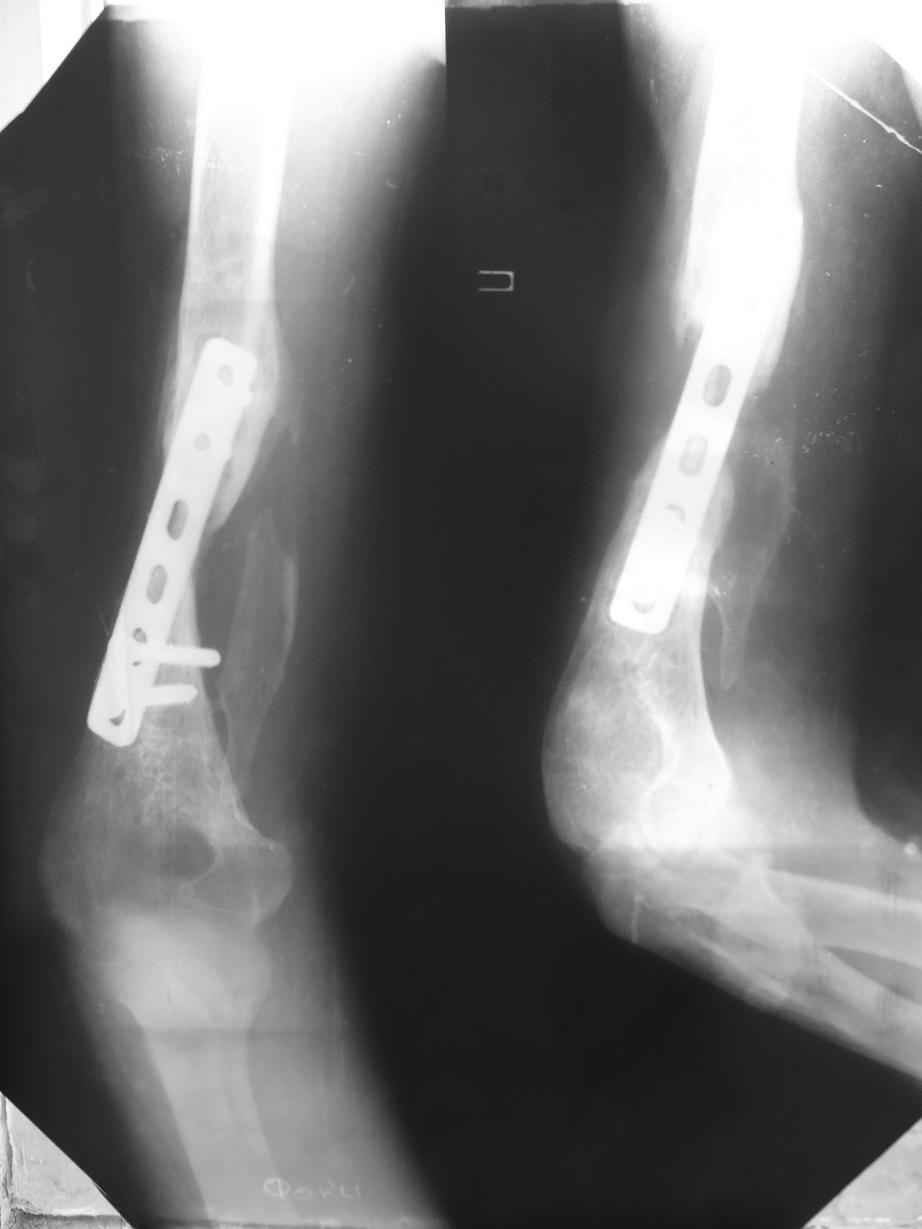

Помогите, пожалуйста, определиться с тактикой!Поступил больной с ложным суставом плечевой кости... Перелом был 2 года назад. Лечился в аппарате 8 месяцев, консолидации не произошло. В феврале 2007 выполнена костная аутопластика, фиксация пластиной (на базе одной из ИК). Сейчас сохраняется ложный сустав, плечо укорочено на 3 см, контрактура обоих смежных суставов, атрофия мышц плеча и плечевого пояса справа. Явлений остеомиелита не отмечалось. Больной - осужденный, сидеть ему до 2012 года.

Уважаемая Татьяна,

Как видно из выступлений коллег, способы фиксации

ложного сустава плеча могут быть различными, кто-то предпочитает аппаратом Илизарова (Соломин), пластинами (Волна) или интрамедуллярным гвоздем (Челноков).

Когда разбирался случай на сайте, и у нас была больная с похожей патологией, ложный сустав после поперечного перелома, леченного год назад где-то и кем-то в другом месте.

Мы не стали делать провокационный метод, который

предложил Корнеев для лечения - применение анаболических стероидов - ретаболила, из-за его бессмысленности, также не согласились с его теорией, что любая операция заблокирует суставы, а наоборот, провели жесткую фиксацию пластиной для раннего восстановления.

Первичную пластину убрали недели 6 назад из переднего оригинального доступа, и из-за подозрительности тканей вокруг пластины, решили провести реконструкцию поэтапно.